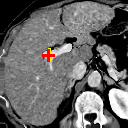

(l) 0.9345

Figure 8 exemplifies the methods on three pairs of scans. Comparison between our methods and traditional methods proves the applicability of our methods to 3D brain registration. Comparison between ADD and DD shows that integrating affine registration subnetwork is effective.